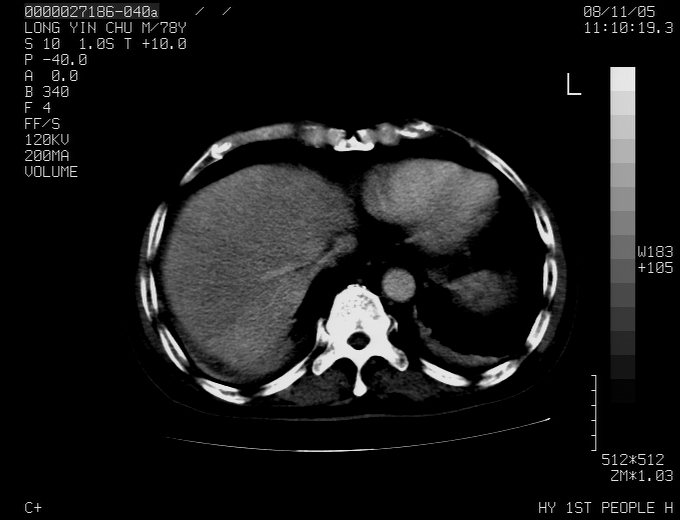

标题: CT16532:M78Y,肝脏病变,请会诊

腹胀,腹痛就诊,男性,78岁,外院b超未见异常。

肝ca,脾肾转移

支持脾肾转移瘤,双侧胸腔积液。

考虑弥漫性肝癌并脾及双肾转移.双侧胸水.

考虑弥漫性肝癌并脾及双肾转移.双侧胸水.  支持

考虑弥漫性肝癌并脾及双肾转移,双侧胸水。